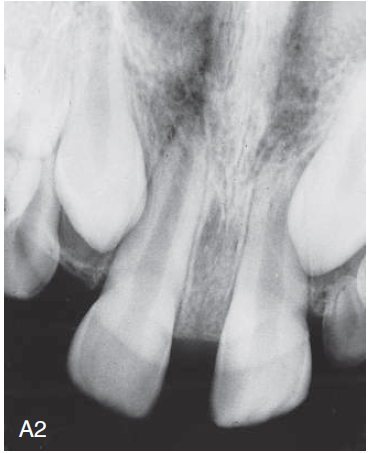

4. (Select ONE OR MORE correct answers)

The radiograph shows evidence of